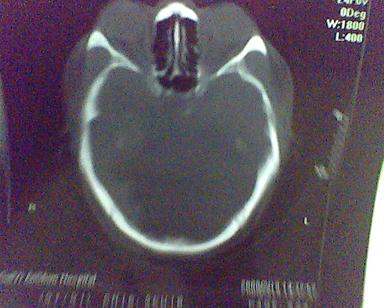

男 31岁 短暂性四肢抽搐 呼叫不应  头胀痛4个多月 无发热 4年前遭棒击头部,当时未到医院检查。余无特殊。病人特穷,未作增强。

请发表看法:脑脓肿?脑膜瘤?。。。

这是一个边缘清晰的等密度的囊性占位.密度比较均匀,周围无水肿,我顷向于脑脓肿的可能性大.

最好是做增强检查 加以鉴别.